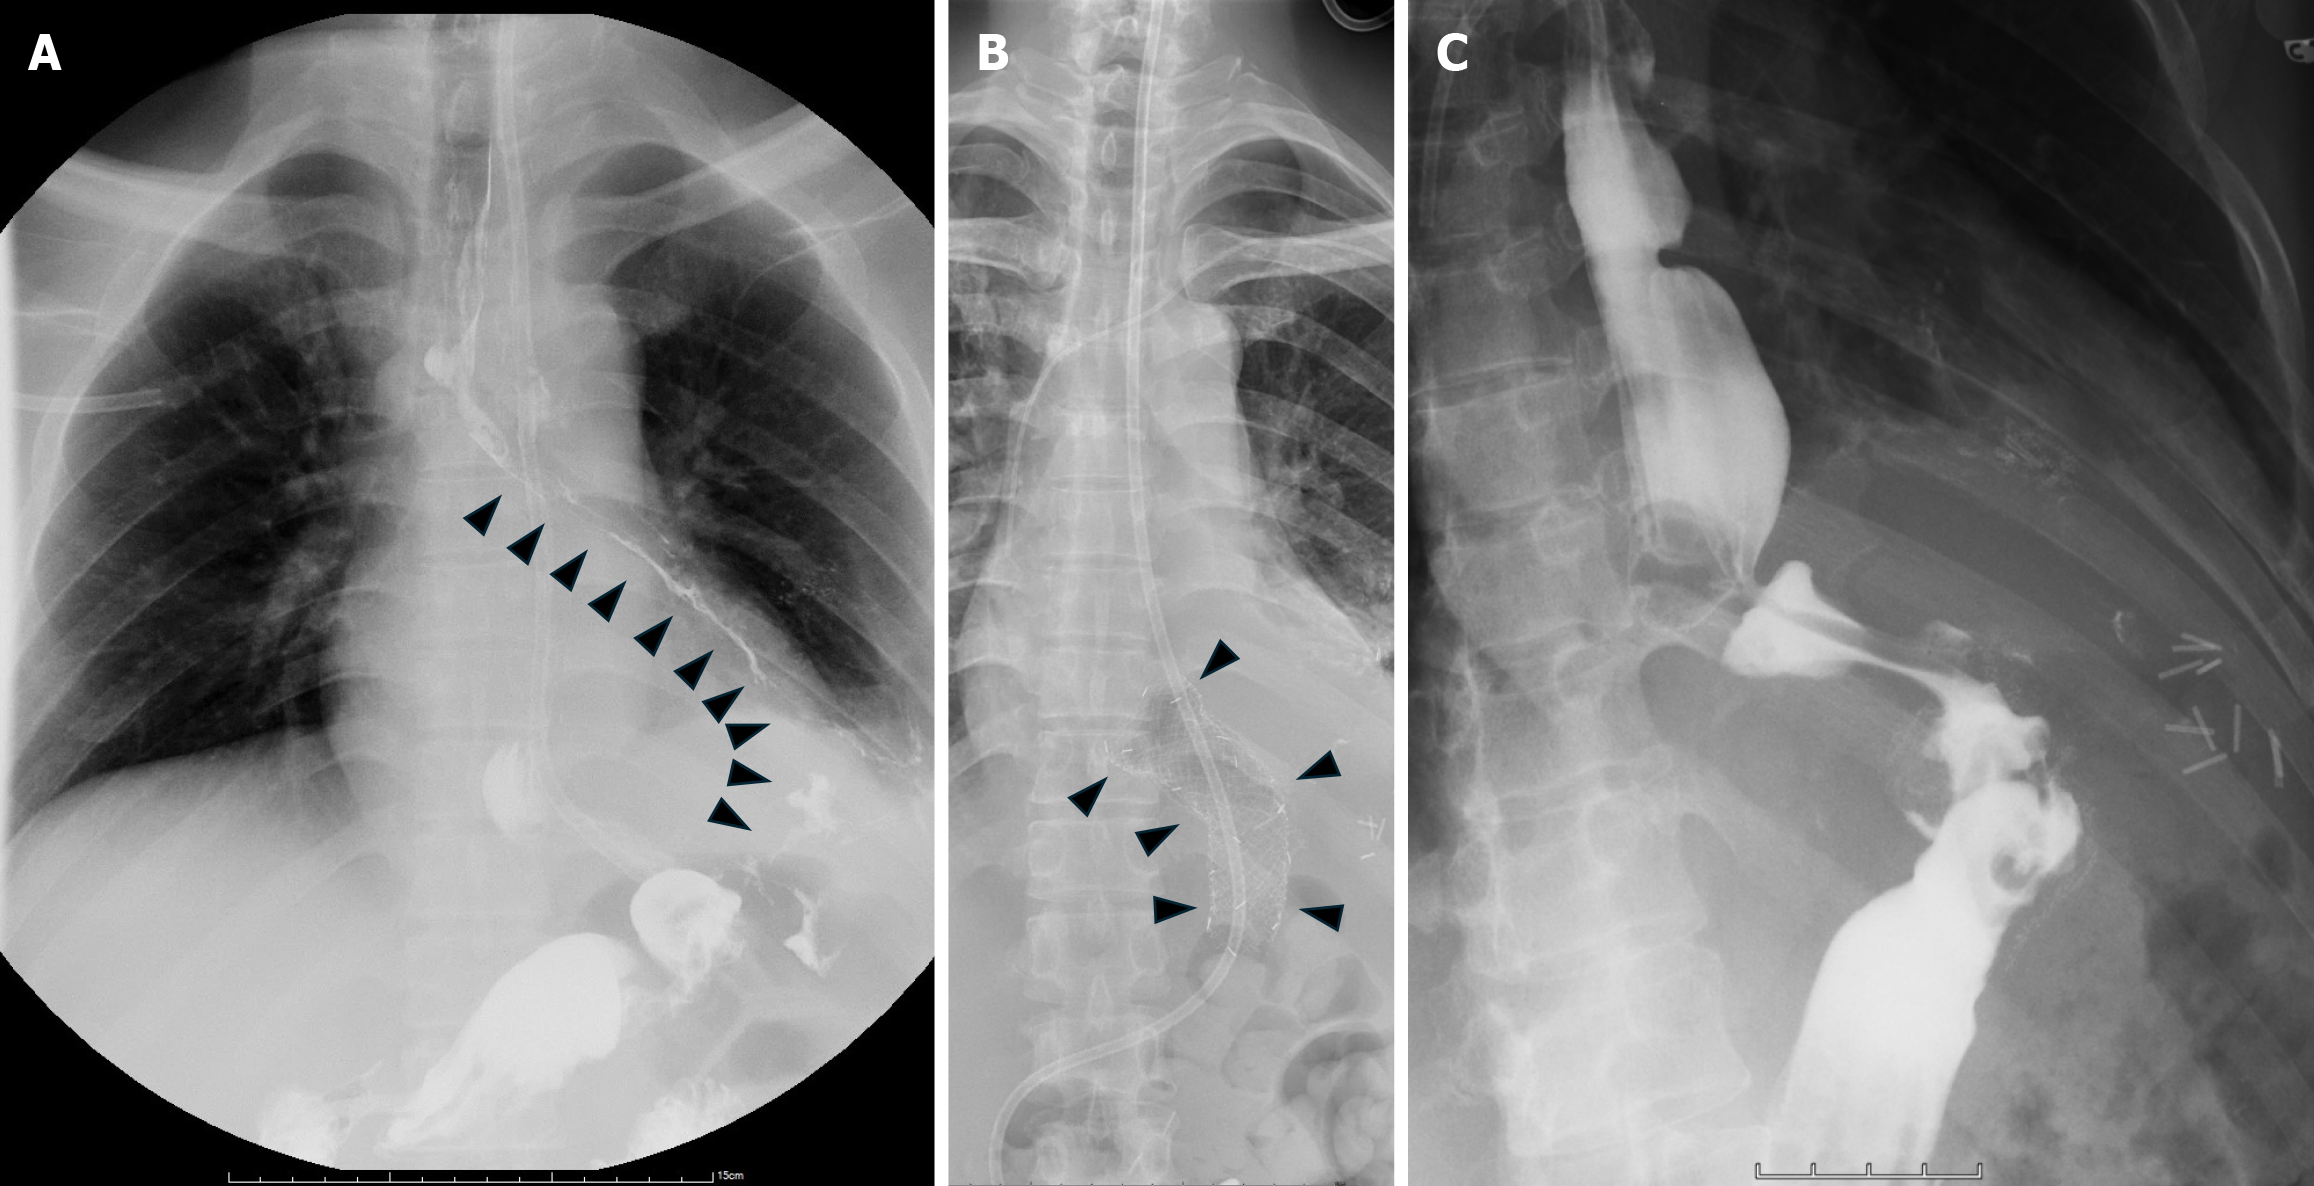

Figure 3 Treatment imaging.

A: Upper gastrointestinal series revealed a left-sided gastrobronchial fistula (arrowhead); B: Chest X-ray demonstrated the proper position of the covered self-expandable metallic stent (arrowhead); C: Upper gastrointestinal series after stent removal showed no contrast leak into the pleural cavity.